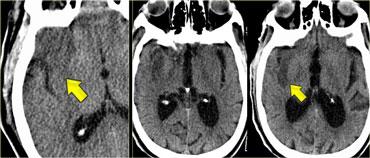

Nhồi máu xuất huyết

15% nhồi máu MCA ban đầu có tính chất xuất huyết.

Xuất huyết được phát hiện dễ dàng nhất trên CT, nhưng cũng có thể được hiển thị bằng chuỗi xung MRI gradient echo.